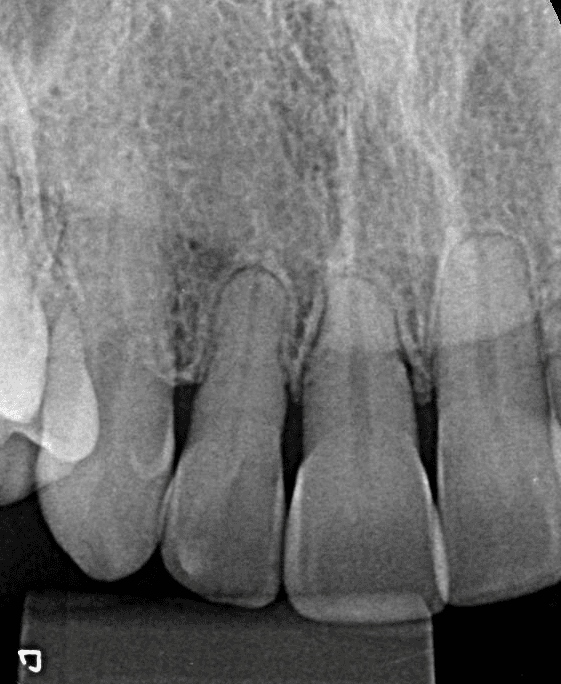

Pacientes infantis na “fase patinho feio”:

A fase do patinho feio é um período natural do desenvolvimento dentário, pode ocorrer dos 7 aos 12 anos de idade, na dentição mista existe a presença de espaços favoráveis para a erupção dos dentes permanentes. O fechamento prematuro desses espaços pode comprometer o processo de erupção e o desenvolvimento ósseo, levando a problemas futuros de oclusão e alinhamento dentário.

Durante essa fase, é essencial monitorar o crescimento e a erupção dos dentes permanentes, evitando intervenções desnecessárias que possam interferir no processo natural.